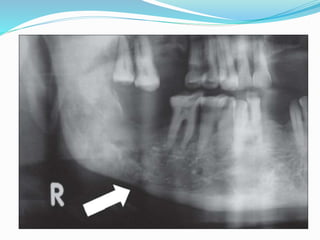

Radiographic Features

 Early changes in bone: is well defined area of bone

resorption within the outer cortical plate of

mandible.

 Later changes: lytic or sclerotic or mixture

 Location : Commonly posterior mandible

 Periphery : ill defined

 Internal structure : A range of bone formation and

resorption occur. The bone pattern is granular.

 Effects on surrounding structures : in rare cases

stimulated periosteal bone formation resulting in

bone formation on outer cortex.

 In the alveolar processes of maxilla and mandible there

is irregular widening of periodontal membrane space.

EARLY LATER